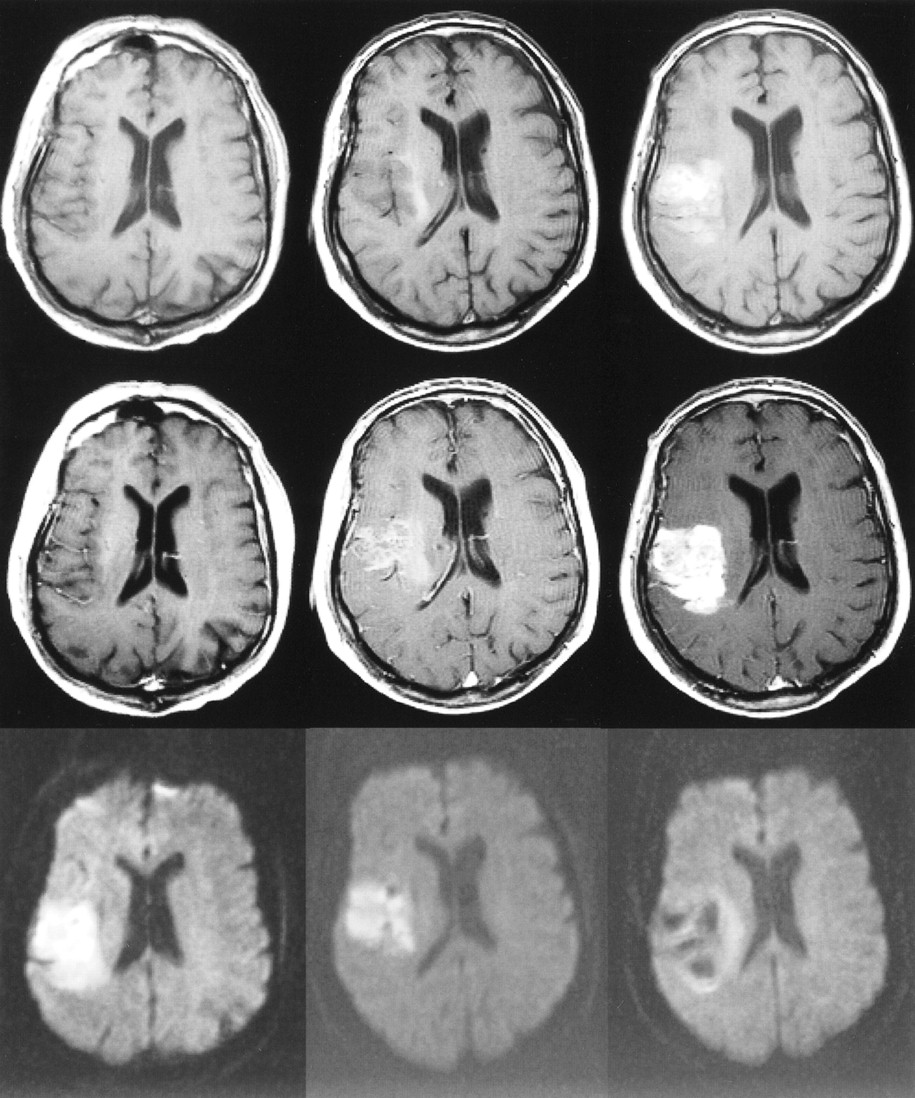

75-year-old woman with dysphasia and weakness in the right arm. The first MR examination (left column) was performed 8 hours after the onset of symptoms, the second MR examination (middle column) was performed on the second day, and the third MR examination (right column) 1 week after stroke. The slice positions are not exactly the same but this does not change the interpretation.

Top row, Unenhanced T1-weighted images (600/14/1) show progressing low signal mass effect of the infarcted tissue.

Middle row, Contrast-enhanced T1-weighted images (600/14/1) show intravascular enhancement over the infarct on the first and second days and moderate cortical and subcortical enhancement 1 week after stroke.

Bottom row, Diffusion-weighted trace images (4000/103/1, in raw image acquisition) show the extent of infarcted tissue as areas of increased signal intensity (bright) in the territory of the left middle cerebral artery.